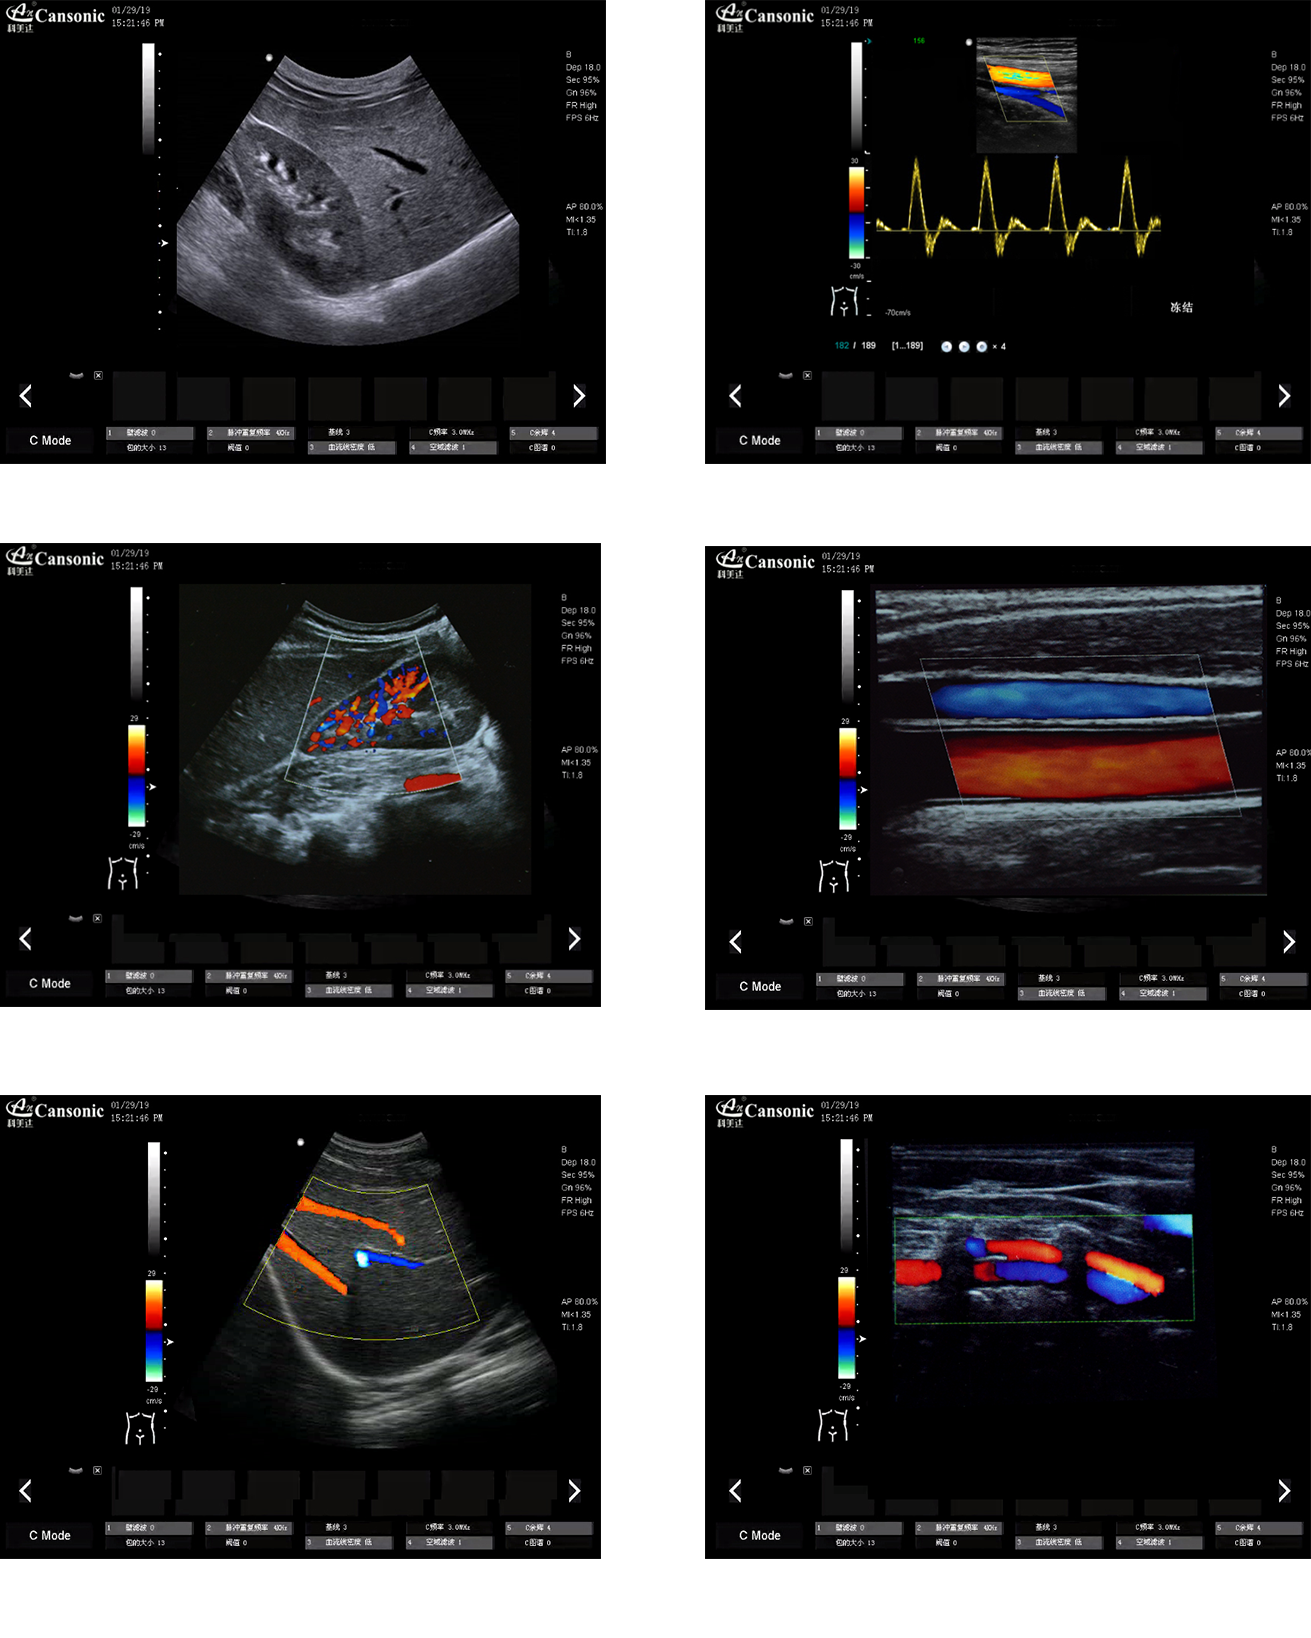

科美達K18圖像實例

1、推車式彩色多普勒全身機,擁有優(yōu)異的圖像質量和突出的血流顯示效果

2、出色的組織均勻性,減少噪聲干擾,提高圖像顆粒細膩度

3、精細血流識別技術,超寬帶非線性造影成像

4、特異性組織成像結合邊緣增強技術,提供可疑病變更多的邊界信息